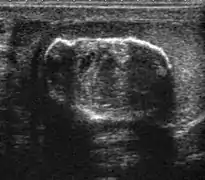

Seminoma is the most common tumor type in cryptorchid testes. The risk of developing a seminoma is increased in patients with cryptorchidism, even after orchiopexy. There is an increased incidence of malignancy developing in the contralateral testis too, hence sonography is sometimes used to screen for an occult tumor in the remaining testis. On US images, seminomas are generally uniformly hypoechoic, larger tumors may be more heterogeneous [Fig. 3]. Seminomas are usually confined by the tunica albuginea and rarely extend to peritesticular structures. Lymphatic spread to retroperitoneal lymph nodes and hematogenous metastases to lung, brain, or both are evident in about 25% of patients at the time of presentation.